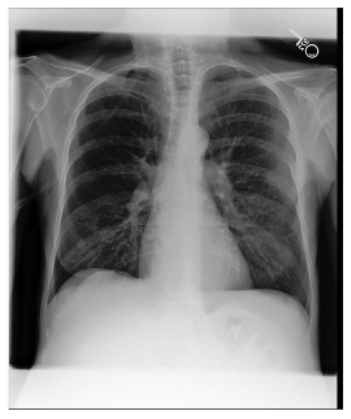

DatasetX-RayGenerated ReportGround Truth

IU X-rayApplsci 16 00470 i001Cardiome-diastinal silhouette is within normal limits of size and appearance. Lungs are expanded and clear of airspace disease. Negative for pneumothorax or pleural effusion.The lungs are clear bilaterally. Specifically, no evidence of focal consolidation, pneumothorax, or pleural effusion. Cardio mediastinal silhouette is unremarkable.